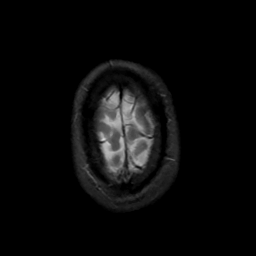

MR Study #4, March 3, 1991 -- Slice #46

[Home][Help][Clinical][Tour 1][Tour 2] Slice 46